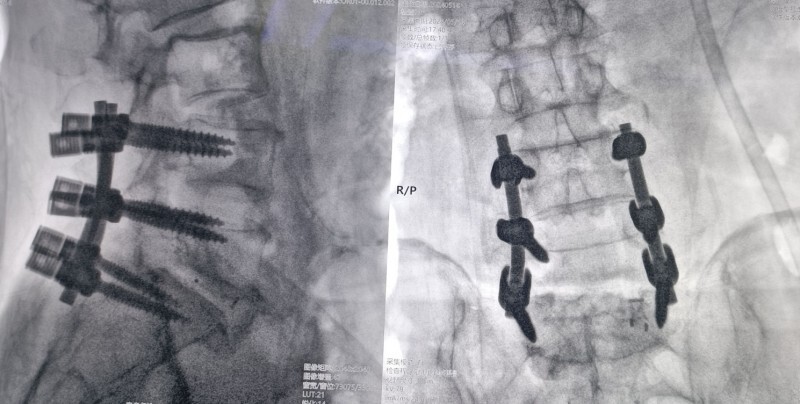

术后片子

方先生,60岁。腰背部疼痛反复发作5年有余,期间也曾在多家医院就诊治疗过,效果不太明显,最近因为病情加重,慕名来我院就诊。5月14日新晨医院骨科为他实行了一台特殊的手术,骨科专家们特别邀请到一名“硬核医生”——机器人“天玑”参与其中。手术进行得十分顺利,这台手术是黄山新晨医院完成的第二台机器人辅助下手术,也是黄山首例“天玑”机器人辅助微创脊柱手术。